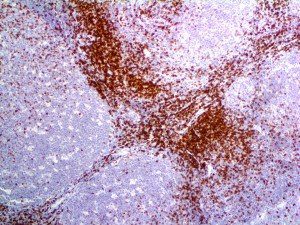

It is the ICU physician who is most likely to witness one of the deadliest manifestations of the abnormal immunological response, the cytokine storm syndrome (CSS). This response is also referred to by some as the cytokine release syndrome (CRS). CSS is characterized by continuous activation and expansion of macrophage and lymphocyte populations, which secrete large amounts of cytokines, causing the cytokine storm. This massive cytokine release is akin to hemophagocytic lymphohistiocytosis (HLH) disease, a syndrome characterized by initial unchecked and persistent activation of cytotoxic T lymphocytes and NK cells.

Clinical and laboratory manifestations of HLH include fever, enlarged liver and/or spleen, neurologic dysfunction, coagulopathy, liver dysfunction, cytopenias (i.e., low levels of erythrocytes, leukocytes, and/or platelets), hypertriglyceridemia, hyperferritinemia, hemophagocytosis, and eventually diminished NK cell activity as the immune system becomes progressively paralyzed. HLH can be familial (primary HLH) or secondary to another disease process (sHLH), such as rheumatic disease, in which it is referred to as macrophage activation syndrome (MAS, characterized by elevated ferritin).